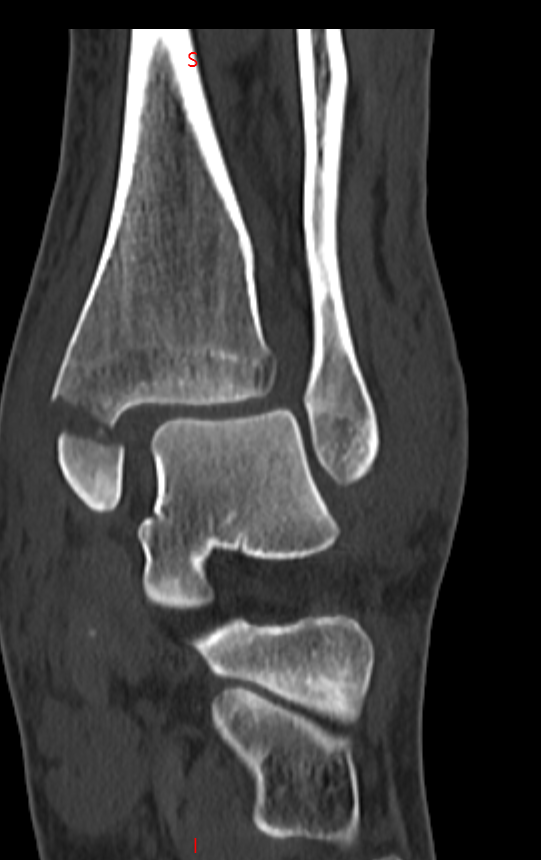

患者因意外受伤后踝关节疼痛、肿胀、无法行走,急诊就诊于我院。

经检查确诊为旋前外旋 Ⅳ 度踝关节骨折,包含腓骨中段骨折、内踝骨折、后踝骨折及下胫腓联合分离,属于临床中结构复杂、稳定性破坏较严重的踝关节损伤。